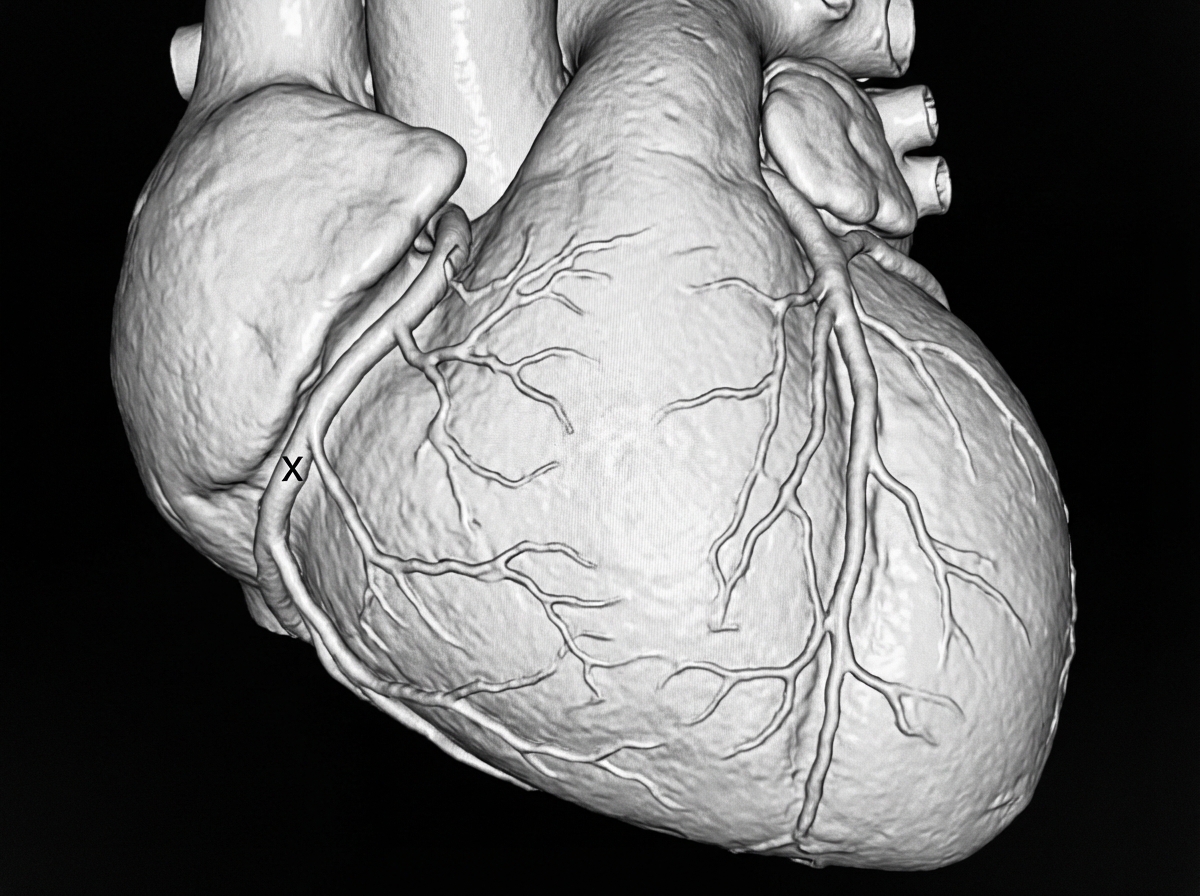

A Coronary CT angiogram shows a blood vessel marked as 'X' coursing around the left side of the heart. Small branches originating from this vessel supply the lateral surface of the heart and are called obtuse marginal branches. Identify the vessel marked as 'X'.

Explanation: ***Left circumflex artery*** - The vessel marked as 'X' is the **left circumflex artery (LCx)**, which branches from the left main coronary artery and courses around the **left side of the heart in the left atrioventricular groove**. - The **obtuse marginal branches** arising from it are characteristic branches that supply the **lateral wall of the left ventricle**. - The LCx supplies blood to the **left atrium, lateral and posterior walls of the left ventricle**, and sometimes the posterior interventricular septum. *Incorrect: Left anterior descending artery* - The LAD courses **anteriorly in the anterior interventricular groove**, not around the lateral aspect of the heart. - It gives off **diagonal and septal branches**, not obtuse marginal branches. - The LAD supplies the anterior wall of the left ventricle and anterior two-thirds of the interventricular septum. *Incorrect: Right coronary artery* - The RCA courses in the **right atrioventricular groove** on the right side of the heart. - It gives off **acute marginal branches** (not obtuse marginal branches) and supplies the right ventricle, right atrium, and (in right dominant systems) the inferior wall of the left ventricle. *Incorrect: Posterior descending artery* - The PDA is a **terminal branch** (usually of the RCA or less commonly the LCx), not a main coronary artery branch from the left coronary system. - It courses in the **posterior interventricular groove** and supplies the inferior interventricular septum.

What is the name of the marked blood vessel shown in the CT coronary angiography image?

Explanation: ***Left anterior descending artery*** - The image illustrates the **left anterior descending (LAD) artery** (marked 'X') coursing down the anterior surface of the heart, adjacent to the pulmonary trunk. - This vessel characteristically runs in the **interventricular groove**, supplying the anterior wall of the left ventricle and the anterior two-thirds of the interventricular septum. *Left circumflex artery* - The **left circumflex artery** typically wraps around the left side of the heart in the **atrioventricular groove**. - It would not be seen coursing along the anterior interventricular groove as depicted by 'X'. *Right coronary artery* - The **right coronary artery (RCA)** originates from the **right sinus of Valsalva** and typically runs along the right atrioventricular groove. - Its anatomical position is on the right side of the heart, supplying the right ventricle and inferior aspects of the left ventricle. *Septal branch of LAD* - Septal branches are **smaller perforating arteries** that originate from the LAD and dive into the interventricular septum. - The vessel marked 'X' is the main trunk of the LAD, not one of its smaller septal branches.